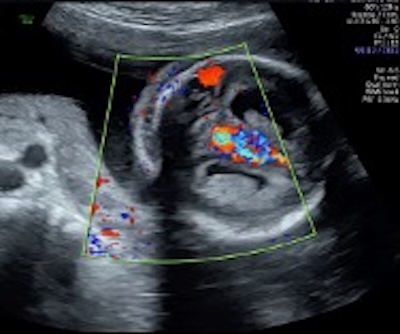

Caso 1 – video

Caso 2. Video